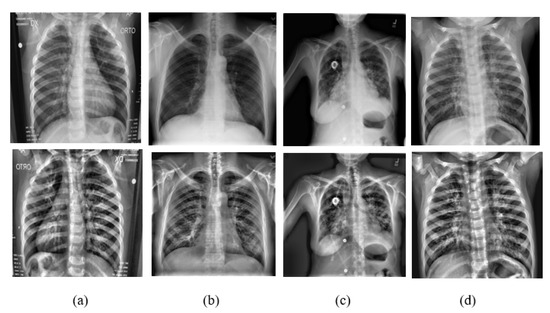

3.3. Dataset